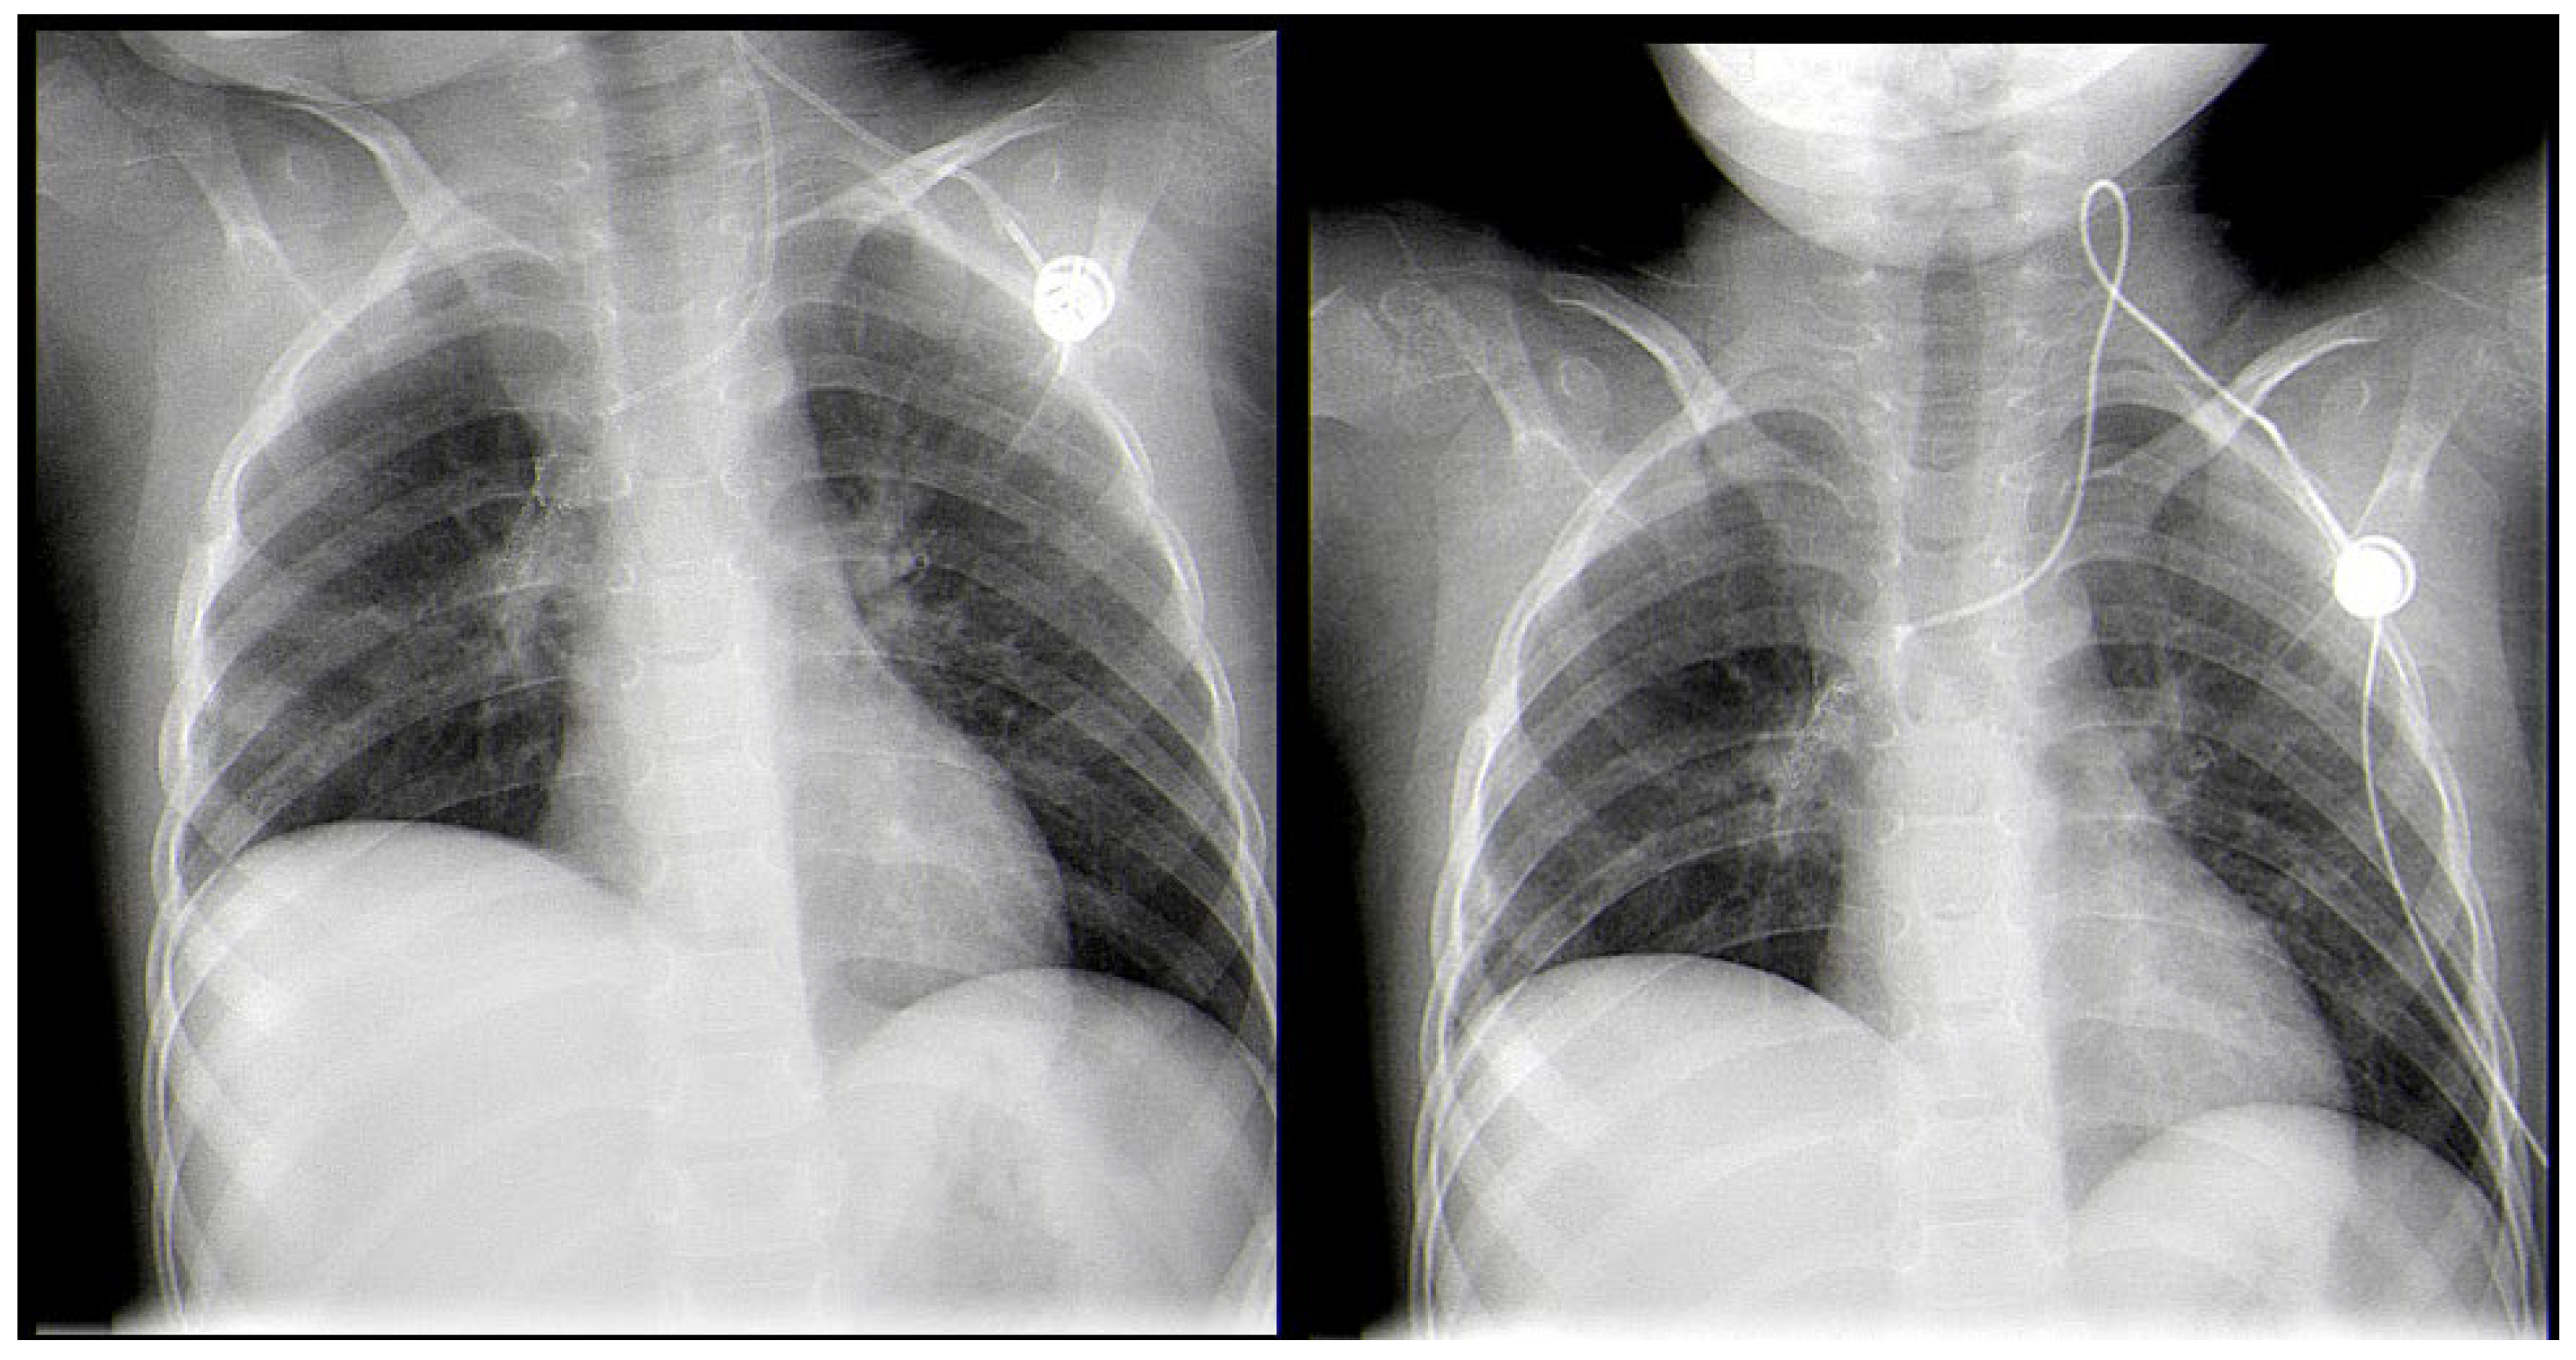

A Rare Case of Rhizomucor pusillus Infection in a 3-Year-Old Child with Acute Lymphoblastic Leukemia, Presenting with Lung and Brain Abscesses—Case Report

Pahnev, Y.; Avramova, B.; Gabrovska, N.; Dontcheva, Y.; Tacheva, G.; Minkin, K.; Kreipe, H.; Yurukova, N.; Penkov, M.; Kartulev, N.; et al. A Rare Case of Rhizomucor pusillus Infection in a 3-Year-Old Child with Acute Lymphoblastic Leukemia, Presenting with Lung and Brain Abscesses—Case Report. Infect. Dis. Rep. 2026, 18, 2. https://doi.org/10.3390/idr18010002